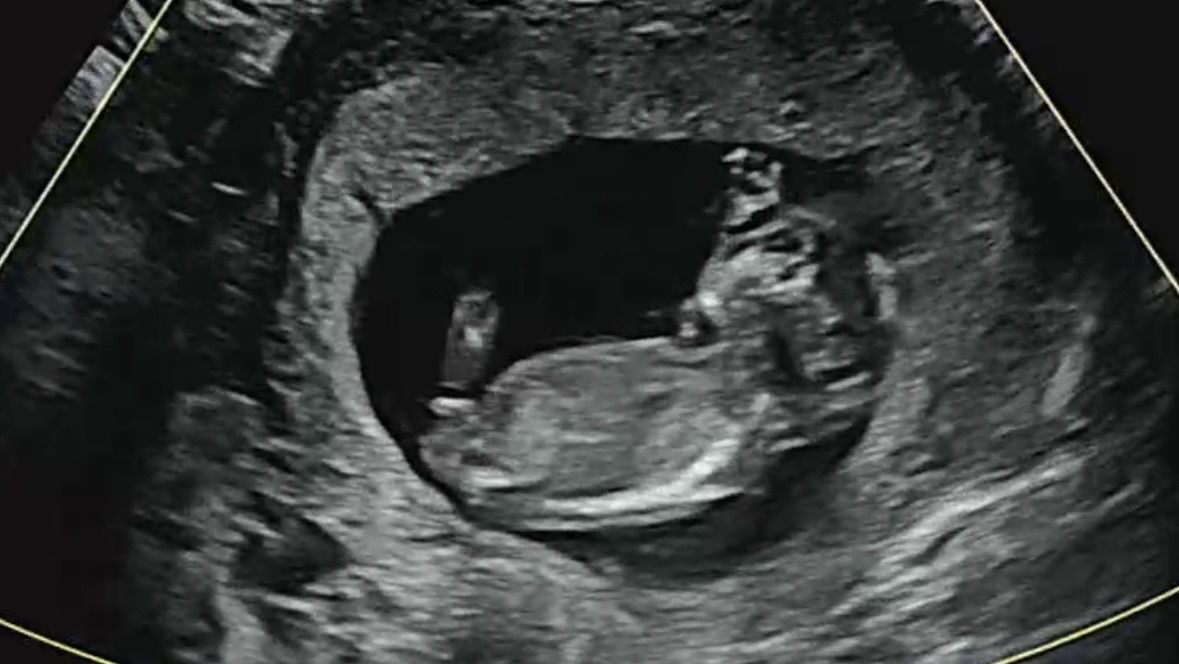

12주3일날 갔는데 아기크기로는 주수 13주라고 하더라구요 그런데 각도법봐도 잘 모르겠어요 투표한번씩 부탁드립니다...! 댓글에도 사진있어요 :)